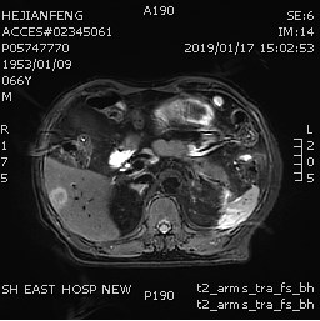

影像学评估:

2019年1月17日

2019年3月27日